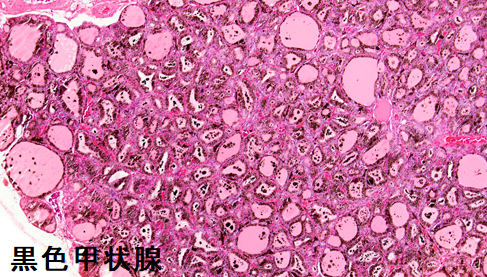

- 黒色甲状腺

黒色甲状腺は無害との報告が多いですが、

- 薬剤性甲状腺炎(無痛性甲状腺炎)も誘発します[Thyroid. 2008 Jul;18(7):795-7.][Horm Res Paediatr. 2019;92(4):276-283.]

- 甲状腺機能低下症を引きおこす可能性もあります[Int J Legal Med. 2006 May;120(3):157-9.][J Pediatr. 2016 Jun;173:232-4.]

黒色甲状腺は、ミノサイクリン非投与例に見られる事もあります。